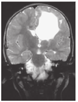

在新生儿期的MRI中,出血病变可能非常显著,但也可能表现仅有某种程度的脑萎缩。婴儿自发性出血病因复杂,这可能决定预后。围生期白质损害与认知缺陷有关;损害越严重,认知的缺陷也就越严重。如果皮质脊髓束和/或基底神经节和丘脑有额外的累及,就可能发生运动障碍。特别注意的是,部分严重早期出血患儿,有较好预后(图9)[10]。

图9

1例宫内严重脑出血患儿的预后 A:孕29周胎儿T2:左侧额叶出血伴脑室扩张,出血周围存在水肿(TR/TE=3 630/90 ms);B:出生后1 d:侧脑室和第三脑室严重扩张,与大脑导水管水平的严重梗阻性脑积水相一致,大脑实质变薄,左侧较右侧显著(第2天进行了手术);C:2岁时,患儿坐在母亲腿上欣赏收到的生日贺卡

Prognosis of a child with severe intracerebral hemorrhage A:fetal magnetic resonance imaging T2-weighted half-fourier acquisition single-shot turbo spin-echo sequence at 29 weeks of gestational age.Arrows indicate left frontal hemorrhage with ventricular extension.The hemorrhage is surrounded by edema (TR/TE=3 630/90 ms);B:computed tomography of the head at 1 day of age,demonstrating severe dilatation of the lateral and third ventricles,consistent with severe obstructive hydrocephalus at the level of the cerebral aqueduct,and thinning of the brain parenchyma,left more than right.She underwent surgery the next day;C:patient at age 2 years,sitting in her mother′s lap,admiring a card she received for her second birthday